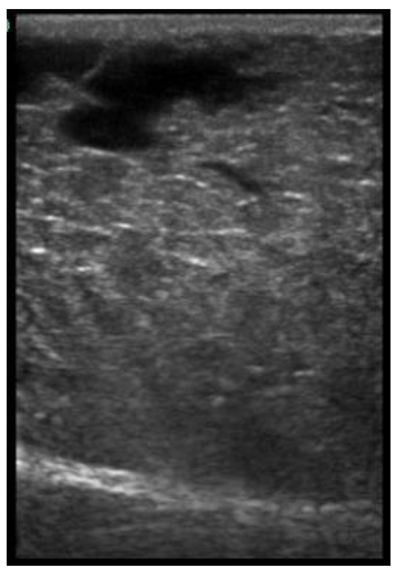

The image processing was undertaken using ImageJ software [28] as used by Abràmoff et al. [29]. The scales between pixels and millimetres were calculated based on the number of pixels, the scanning depth (mm), and the transducer width (mm) (Figure 4). This method relies on the ability of the operator to interpret and identify lines on the images. To standardize the assessment compartment depth, drawing templates were created for each time point as used by Molenaar et al. [30] and included four representative images from four different yearling ewes with and without the lines drawn for each compartment (Appendix A). The total depth of mammary gland conservative (MTc) was the smallest likely demarcation (abdominal wall) of the mammary gland (Figure 5a), and total depth of the mammary gland generous (MTg) was the largest likely demarcation of the mammary gland visible on the image [30] (Figure 5a). The MTc, MTg, fat pad (FP), parenchyma (PAR), and gland cistern (GC) depths were estimated at the deepest point for each sub-compartment, excluding the skin layers, using the straight tracer (Figure 5a) and were expressed in millimetres.

Figure 5.

(a) Demonstration of delimitations of the mammary total depth conservative (MTc) and generous (MTg), mammary gland cistern (GC), parenchyma (PAR) and the fat pad (FP) and (b) Demonstration of randomly positioning of regions of interest (1, 2, 3) in the parenchyma.

Appendix A. Drawing Templates of Mammary Ultrasound Images in Late Pregnancy, Early Lactation and Weaning in Yearling Ewes

Drawing template of mammary ultrasound images in late pregnancy (107 days of pregnancy; P107) in four different yearling ewes.